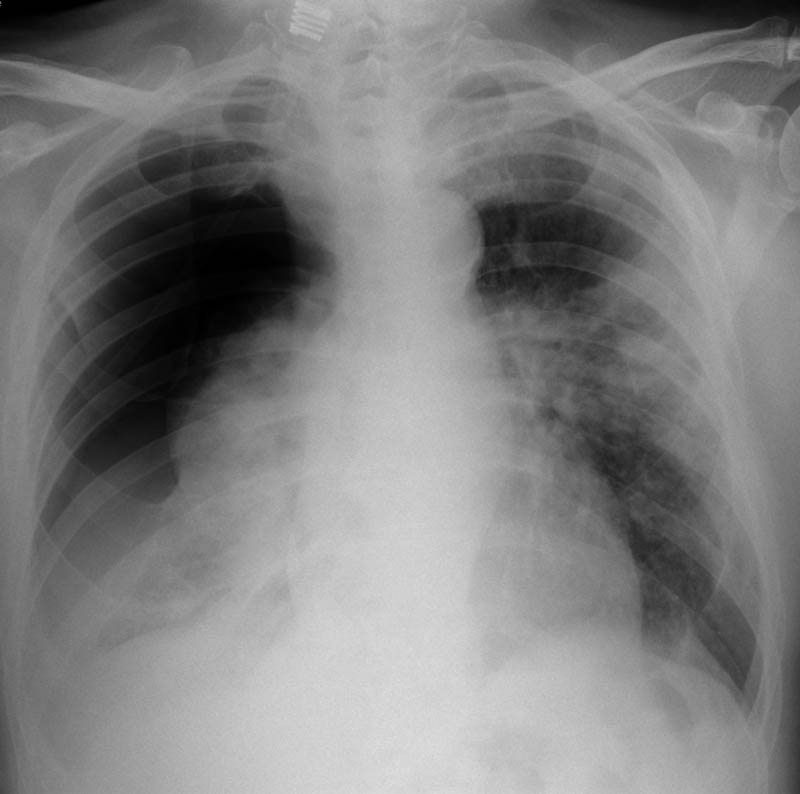

Fibrosis pulmonar. ICC.